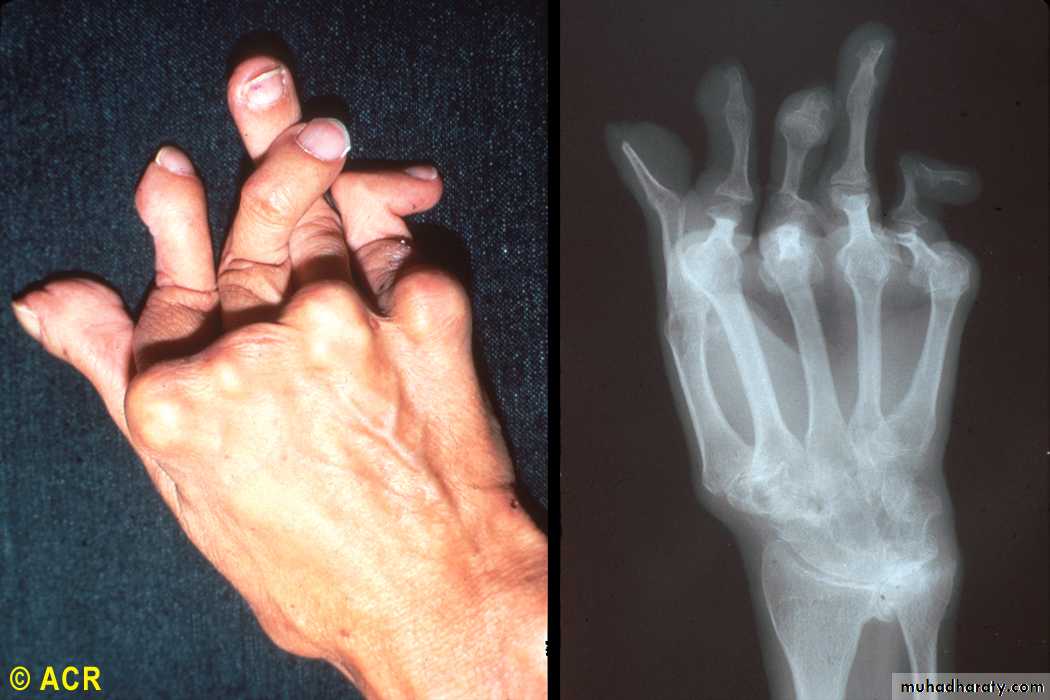

Rheumatoid arthritis: arthritis mutilans, hand (clinical and radiograph)

the most helpful laboratory procedure. The fluid is inflammatory, with more than 10,000 white blood cells and a predominance of polymorphonuclear leukocytes, typically 80% or more. Rheumatoid factor, an IgM antibody directed to IgG, is found in 80 to 90% of patients with RA.... XR-Findings

Peri articular osteopenia

Marginal erosions (at least months of persistent activity)

Joint space narrowing (cartilage loss)

Ankylosis (wrists)

Deformities